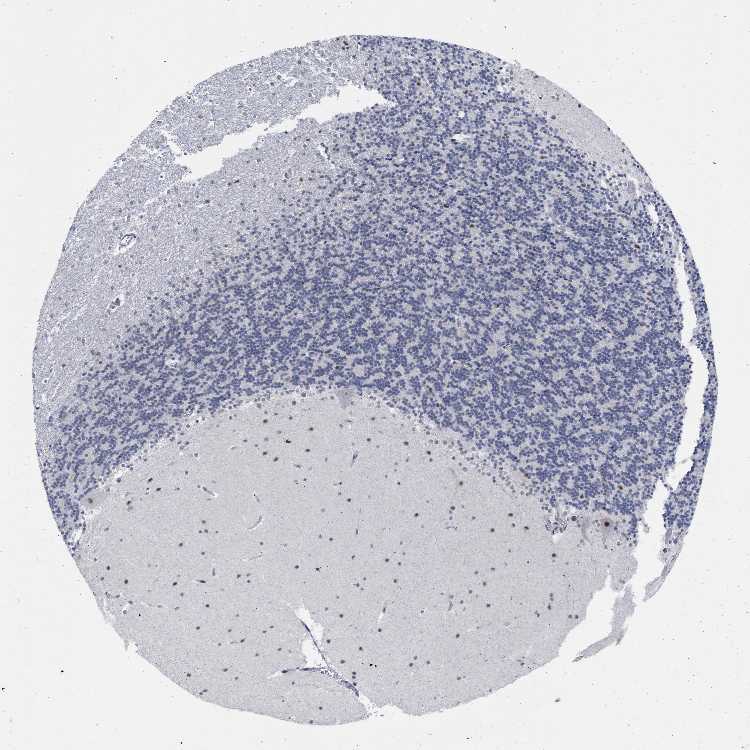

BRAIN CEREBELLUM Show tissue menu

CEREBELLUM - Expression summary

Protein expression

Cerebellumi

On the top, protein expression in current human tissue, based on all annotated cell types, is reported with the units not detected (n), low (l), medium (m) and high (h). Underneath, protein expression in each annotated cell type are reported using the same units.

Protein expression data is based on knowledge-based annotation. For genes where more than one antibody has been used, a collective score is set.

CEREBELLUM - Antibody stainingi

Antibody staining in the annotated cell types in the current human tissue is reported as not detected, low, medium, or high, based on conventional immunohistochemistry profiling in selected tissues. This score is based on the combination of the staining intensity and fraction of stained cells.

Each image is clickable and will lead to virtual microscopy that enables deeper exploration of all samples and also displays staining intensity scores, fraction scores and subcellular localization as well as patient and tissue information for each sample.

Antibody HPA017911Antibody HPA048803

Purkinje cells MediumHigh

Cells in granular layer Not detectedMedium

Cells in molecular layer MediumMedium